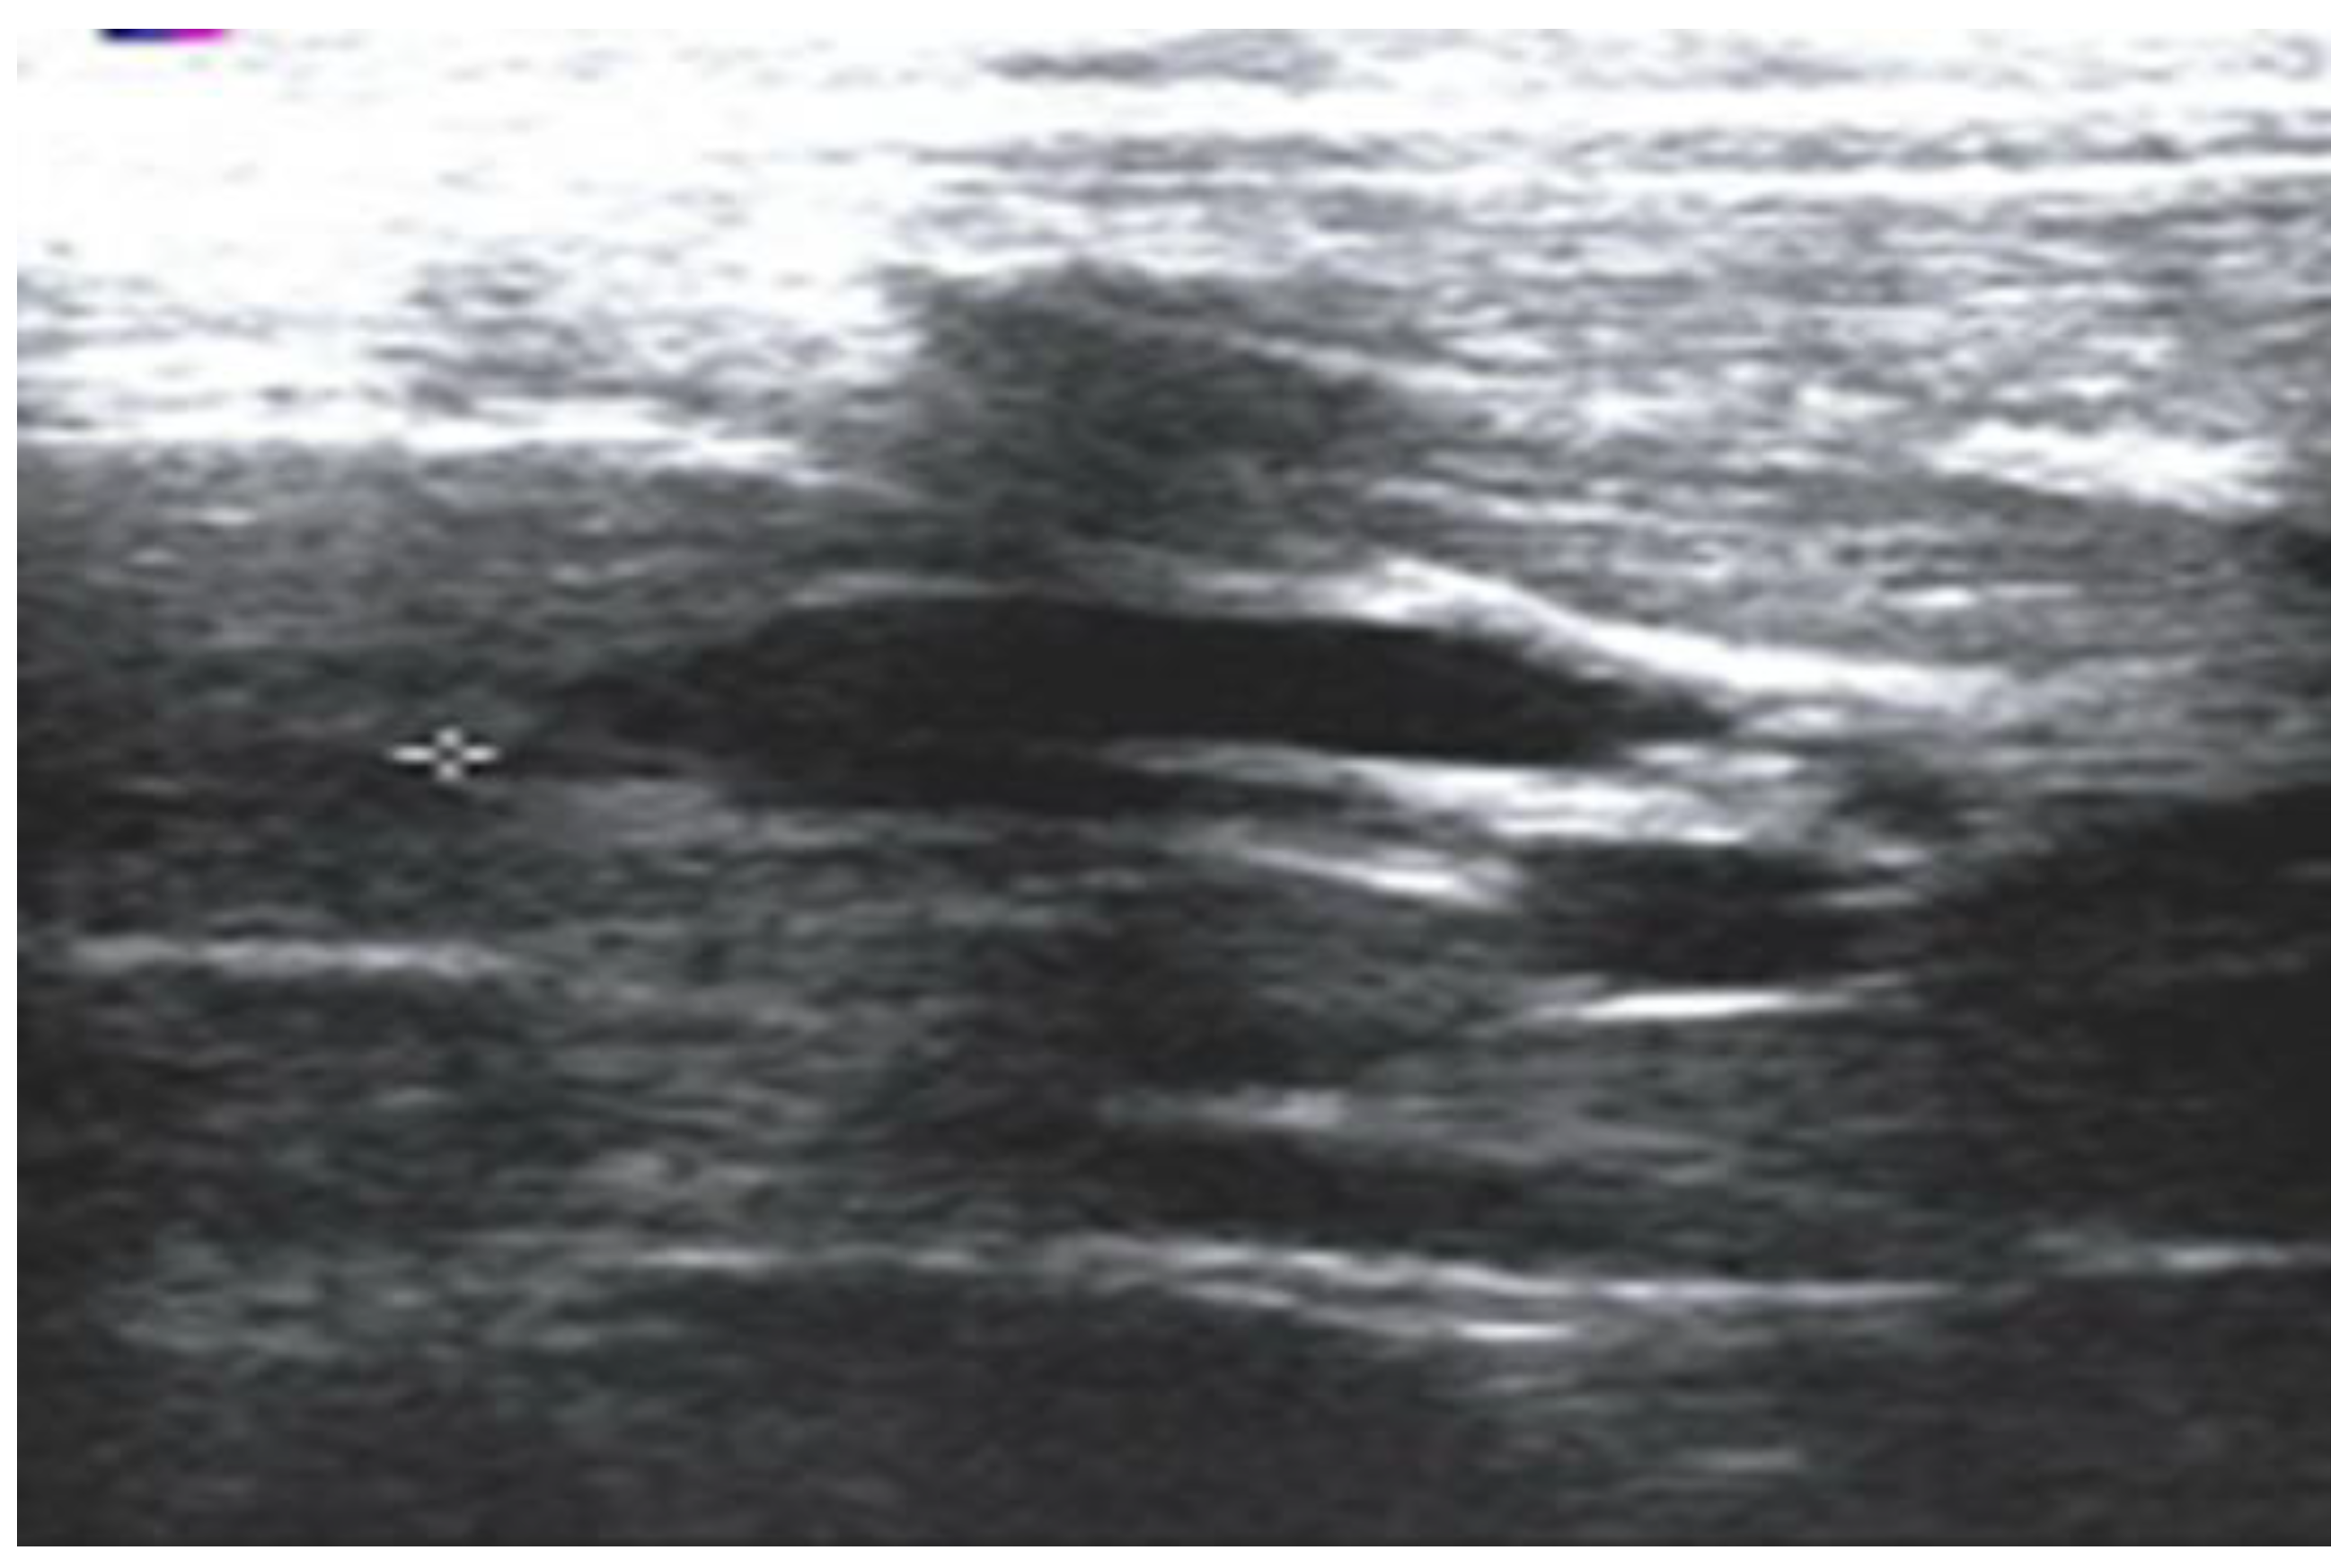

All patients enrolled in the study underwent either standard Roux-en-Y hepatico-jejunostomy or hepatico-duodenostomy. The FFCC is defined as a condition meeting all of the following criteria: (a) fusiform (non-cystic) dilatation of the CBD, with a diameter between 5 and 10 mm, exceeds the upper limit of normal for age but lacks classic cystic morphology; (b) an APBJ has been confirmed through magnetic resonance cholangiopancreatography (MRCP), endoscopic retrograde cholangiopancreatography (ERCP), or intraoperative cholangiography; (c) clinical presentation suggests biliary or pancreatic pathology (e.g., abdominal pain, recurrent fever, jaundice, and pancreatitis); (d) no other identifiable structural hepatobiliary anomalies. Standard diagnostic protocol included abdominal ultrasonography (Figure 1).

Figure 1. An abdominal ultrasound of a 2-year-old girl shows a dilated CBD with a diameter of 8.2 mm.